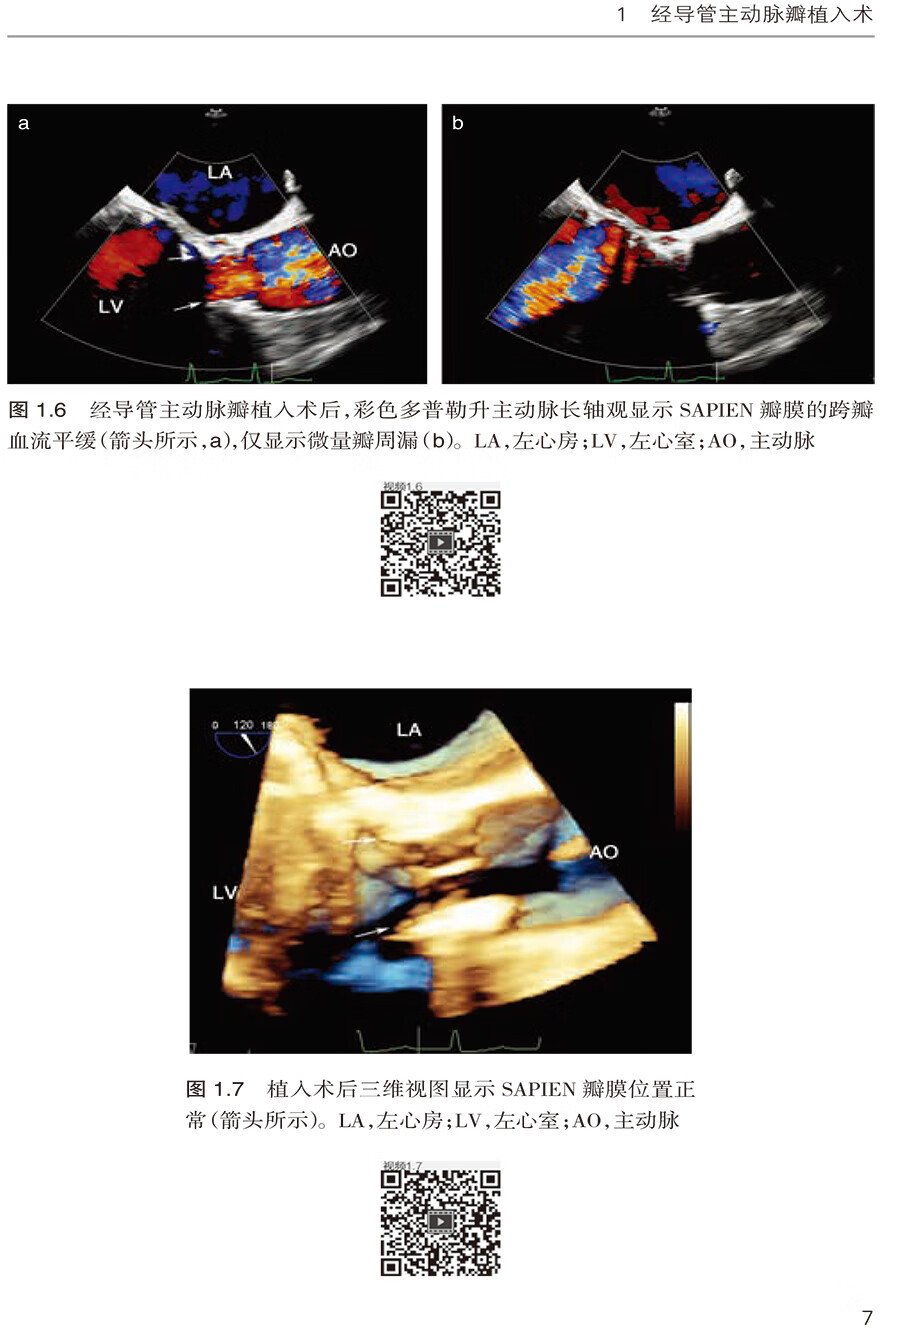

1.2 经心尖SAPIEN 瓣膜植入术 /3